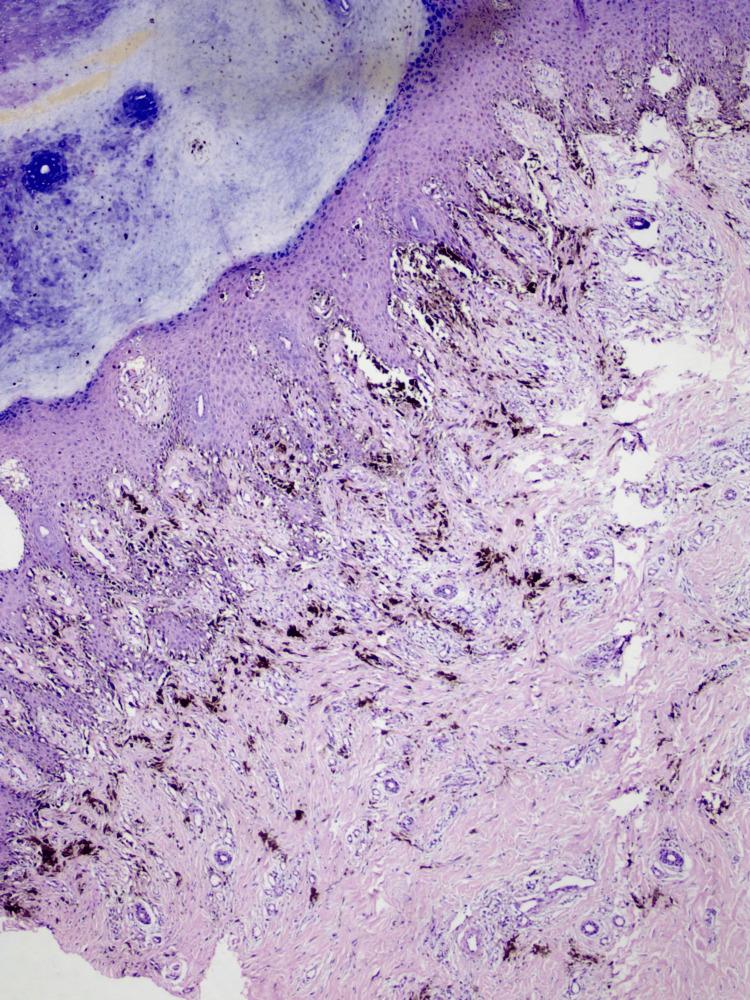

Acral lentiginous melanoma (ALM) is named so for its site and histological orientation. It is an infrequent form of melanoma that usually presents with lesions on the palms, soles, or nails. Although rare, it's the most commonly discovered subtype of melanoma in the non-Caucasian population, including Africans, Chinese, Koreans, and Latin Americans. It's most likely to be diagnosed in the sixth or seventh decade of life. Acral lentiginous melanoma can clinically mimic ulceration, verrucous lesions, onychomycosis, subungual hematomas, vascular lesions, and infections. Here, we are presenting the case of a 65-year-old male who was admitted to the surgery ward in Acharya Vinobha Bhave Rural Hospital with a chief complaint of a lesion over the plantar surface of his left foot for the last one or two years and was referred to the Department of Dermatology for the same. The lesion was sighted by the patient a long time before his visit to Acharya Vinobha Bhave Rural Hospital. A physical examination showed a blackish, poorly delineated soft tissue lesion on the left heel. An excisional biopsy and proper management were carried out for the patient. Patient education and greater awareness about this tumor and its early detection can serve as important weapons to increase the patient survival rate and prognosis of acral lentiginous melanoma.